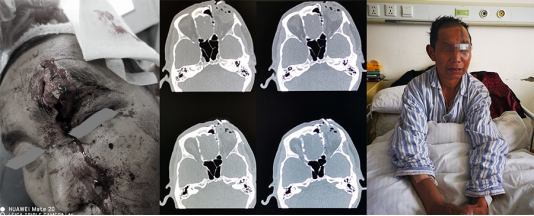

在急诊,牛角巨大的冲击力留下的骇人惨状令人触目惊心:患者眶上缘及额骨骨折脱位外翻皮外,前颅底组织破碎、残缺,筛窦、额窦开放,颅底硬膜缺损,脑脊液外渗,额底脑组织一处盲管伤。

毫不犹豫,快速准备,急诊予以损伤脑组织清创手术。

尽快!手术清创缝合

颅底骨折断端把硬膜撕扯残缺不整,正常的组织界限已经没有。完成了脑内挫伤组织的清创。我们在显微镜下仔细寻找着硬膜的断端,游离出1-2mm的空间,予以一期自体筋膜修补,水密试验确保缝合确实。开放的副鼻窦用自体筋膜封闭。双层封闭措施对于开放性颅脑创伤患者的预后改善是有很大帮助的。

此时眼球的眶脂体包膜就在视野之下。也许是患者在牦牛来袭的一瞬间下意识的低头,让眼球躲过了一劫。联合眼科检视解剖上完整无大碍。骨折片回纳固定,重建眶部及颅底结构,不至于术后出现面部的明显塌陷。再美容缝合额面部皮肤,尽可能地减少疤痕。

所幸患者术后恢复顺利没有出现颅内感染、脑脊液鼻漏、复视、眼球活动障碍等并发症,顺利出院。